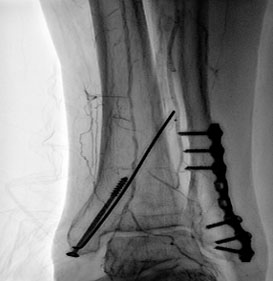

Второй этап – эндоваскулярная хирургия. Без перекладывания пациента, на том же операционном столе, в работу вступила бригада эндоваскулярных хирургов. Следующим этапом выполнено стентирование и баллонная ангиопластика сосудов нижней левой конечности:

Через подвздошно-бедренный шунт, установлен интродьюсер (порт служащий для заведения в сосуд хирургического инструментария), далее по рентген контролем позиционирован и имплантирован стент в подвздошную артерию с переходом на ранее установленный шунт.

Интродьюсер, установленный в подвздошно-бедренный шунт |